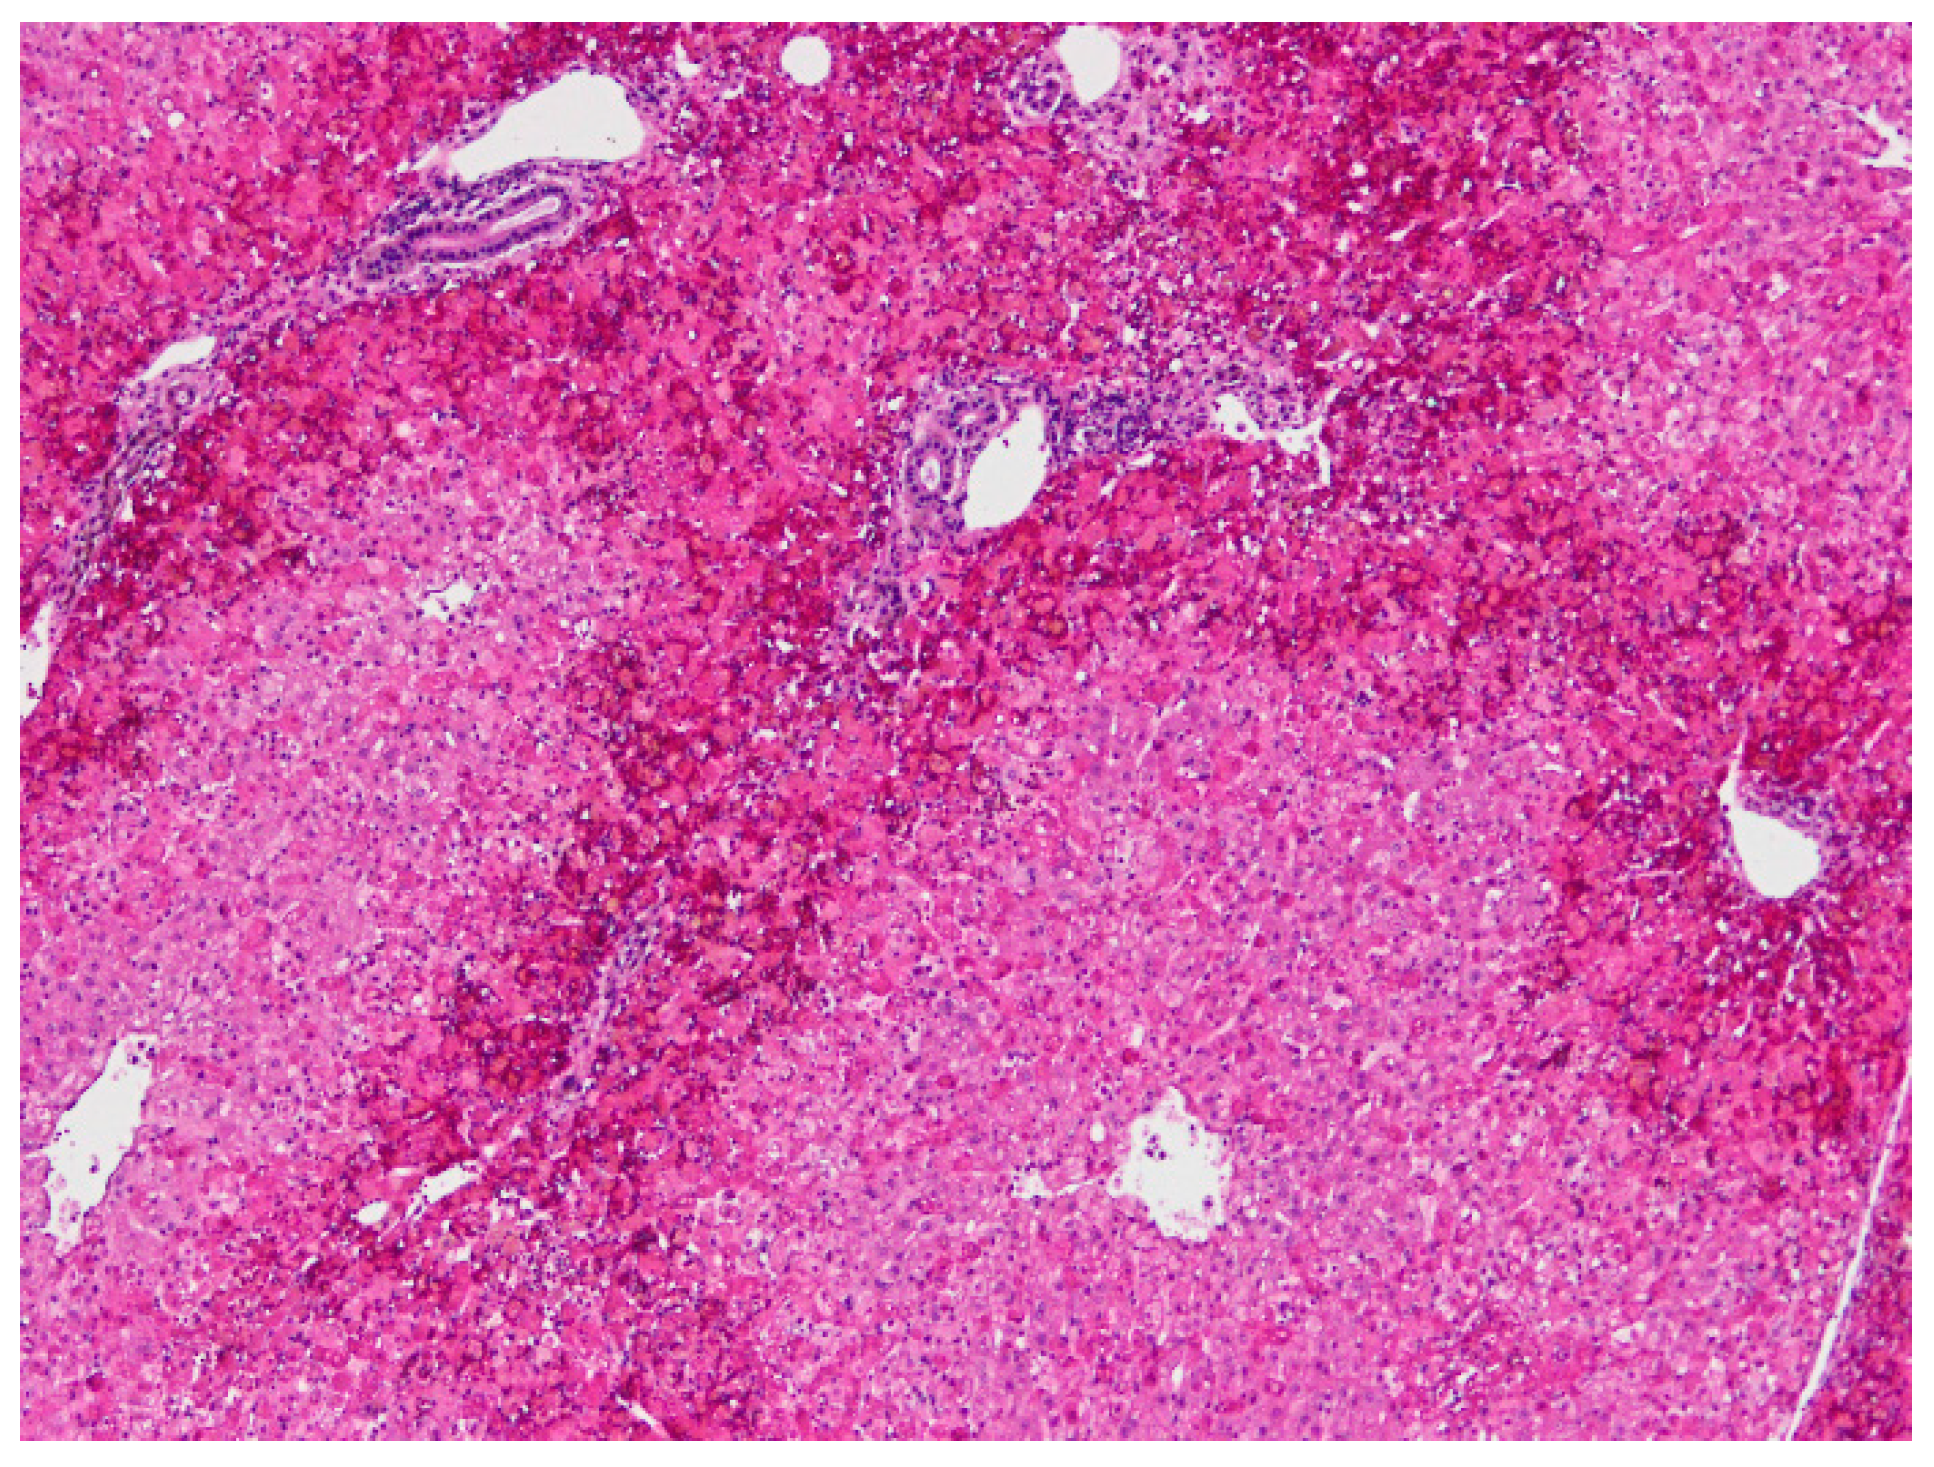

The following microscopic lesions were observed: Liver: severe generalized perilobular haemorrhagic necrosis (Figure 3 and Figure 4). Discrete infiltration by mononucleated inflammatory cells, mainly macrophages and lymphocytes, around portal triads. Fine brown pigment in the cells of the portal bile ducts. Spleen: diffuse necrosis of the entire red pulp revealed by deposition of fibrinoid acidophilic material drawing serpiginous patterns in the parenchyma (Figure 5). The regular presence of lymphoid follicles around central arterioles. Pancreas: interlobular oedema and necrosis of adipocytes, both intralobular and interlobular. No changes were present in the secretory cells. Stomach: no significant changes were observed. Small intestine: Necrotic enteritis, particularly in the duodenum, with loss of villi and deposition of fibrin in the proximal mucosa (Figure 6). Kidneys: the areas of surface retraction in both kidneys corresponded to segmental fibrosis affecting cortex and medulla. In these areas, there was a loss of tubules and glomeruli, which were moderately congested. No microbial agents were identified in any organ and the results of the microbiological analysis were also negative.

Figure 5. Spleen. Severe diffuse fibrinoid necrosis of the red pulp. The eosinophilic material fibrinoid material is very abundant between the lymphoid tissue that surrounds blood vessels (H&E, 40×).